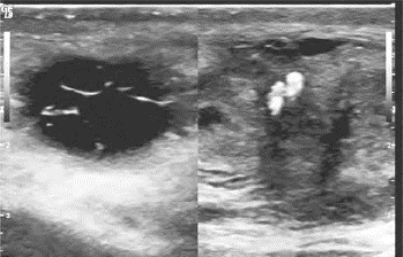

图31-9 精索静脉曲张声像图(见彩图42)

Valsalva动作后,精索静脉管径增加

2.CDFI和频谱多普勒显示静脉内血流(因血流速度极低,甚至淤滞)仅在Valsalva动作后,静脉内血流速度增加。当有精索静脉曲张时,表现为睾丸和附睾上方精索周围有多个条索状或圆形管状暗区,即为扩张迂曲的精索静脉、扩张的静脉管径通常在2.5~4mm。